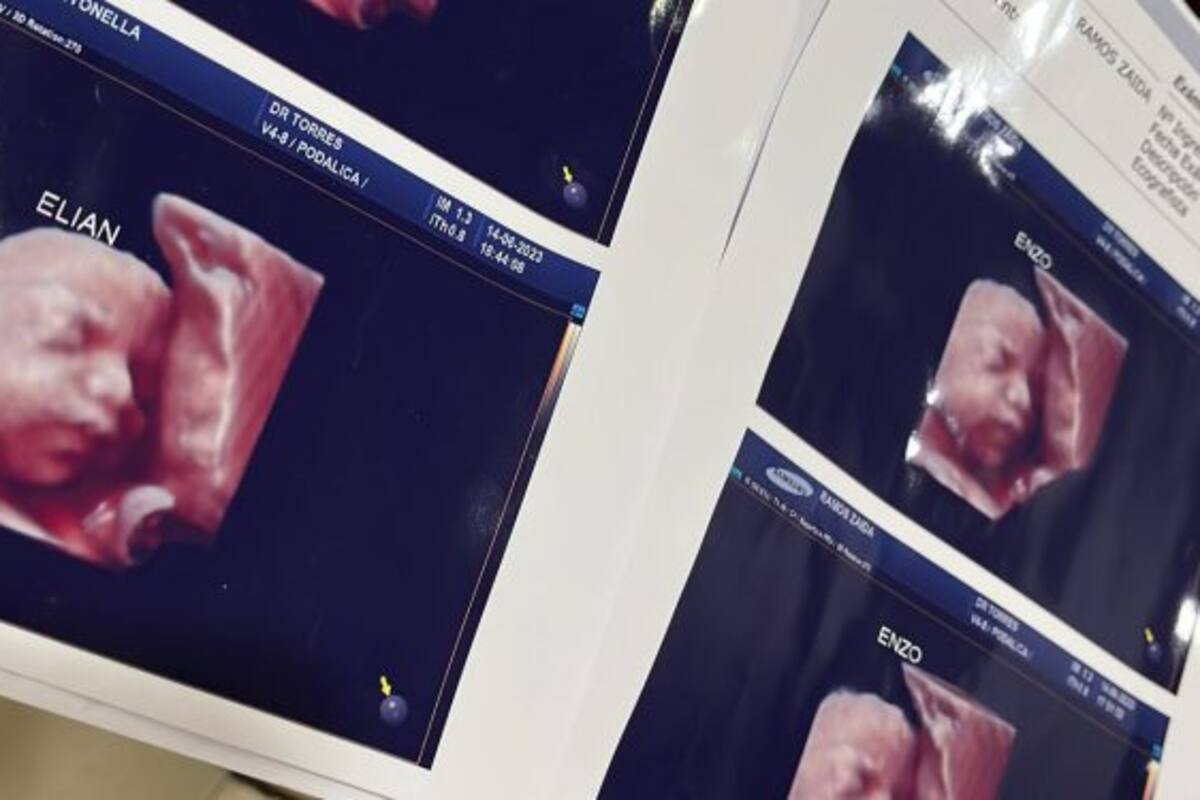

Cuando una joven embarazada subió a TikTok la ecografía del hijo que llevaba en su vientre no imaginó lo que se iba a generar. Inmediatamente, Antonella Roglan reconoció en esa imagen a quien creía que era su hijo. Ambas intentaron evitarlo, aunque después de un tiempo llegaron a una conclusión terrible. Al parecer, la clínica privada en la que se atendían, en Formosa, las había engañado: habría usado la misma ecografía con ellas y quizás con varias mujeres más.

Las fotos 5D de las imágenes se convirtieron para ellas en una pesadilla. No tienen dudas de que se trata de una “estafa”, según dio cuenta el sitio Noticias de Formosa. “Ya nos lo habían dicho, pero nos resistíamos a creer”, afirmó una de ellas. Hasta el momento, son cuatro las mujeres afectadas, según dijo Roglan en su cuenta de Twitter.

“Por ahora somos tres mamás a las que una clínica estafó con una foto de un bebé que no es el nuestro”, afirmó Roglan en su cuenta de Twitter. “Está de más decir que encima que cobran carísimo uno se va ilusionado por ver a su bebé y tener un lindo recuerdo. Estamos en busca de más mamás con el mismo bebé”, dijo.

Más tarde, la mujer comentó que habían descubierto que esa misma imagen se la habían dado a otra familia y le habían hecho creer que se trataba de una niña, según expresó. En los primeros casos, la imagen fue entregada a mamás que esperaban varones. Así, no tenían dudas de que habría varias personas afectadas.